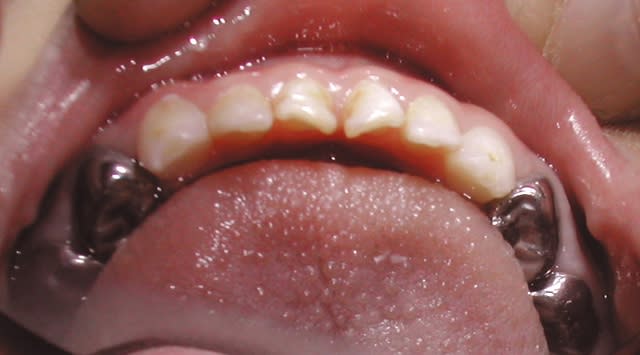

je déterre ce post suite à une consultation de ce matin.

la patiente est une jeune femme, tout ce qu'il y a de plus normal.

les soins ont moins d'un an

bien entendu c'est cassé

voilà, bonne matinée

Sérieusement, pas simple à gérer psychologiquement (cliniquement c'est facile par contre)

2 CVI + tenon , dans ces conditions, on va dire 15 minutes maxi , peut être une matrice tofflemire mais c'est même pas certain.

comment trouver les mots pour expliquer la situation et rester confraternel?

on a tous dans les placards des soins peut être borderline, mais là c'est compliqué à défendre.

et d'autant plus nase que les traitements endo ne sont pas mal du tout

C’est pas lui qui les a faits. Y’a une pêche en mésial de la 6.

Normale avec parodontite

c'est juste le plus distal qui n'est pas parallèle aux autres.